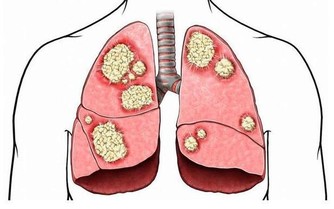

腎臟是人體器官中很重要的一個排毒器官,它一旦出現問題,體內的連環效應就會凸顯,身體就會出現各種各樣的疾病。

據調查統計,目前全球大約有1/10的人慢性腎臟疾病。根據我國最新的流行病學調查結果顯示,在普通人群中慢性腎病的患病率約為12.6%,也就是說,十個人中至少有一人患有慢性腎病。

腎功能隨著年齡增大會逐漸衰退,但是生活中有些不良的生活習慣或行為,也是腎功能受損的重要因素。